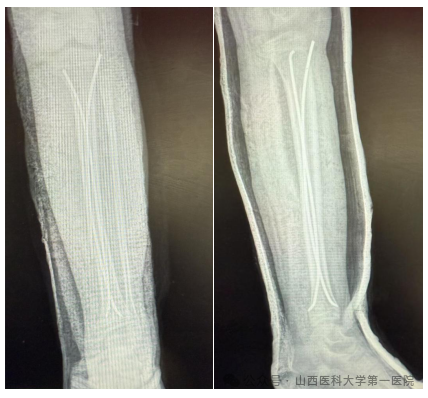

手术切口取双侧胫骨近端骨骺下方1cm长度仅约1cm的纵行切口,预先体外将弹性髓内钉预弯,预计弧顶位于骨折断端,C臂透视下行骨折断端手法复位,复位满意后从两侧切口依次插入2枚弹性髓内钉,使各自弧顶在骨折断端处呈“)(”,给予骨折断端足够支撑,避免骨折断端移位。手术过程顺利,术后复查拍片可见骨折复位满意。

杨自权主任表示儿童胫腓骨骨折是儿童长骨骨折的第三常见部位(仅次于前臂及股骨),主要伴随有影响生长发育的风险,针对儿童胫腓骨骨折这一特殊患者人群,使用儿童弹性髓内钉治疗具有创伤小、疤痕少、闭合复位、恢复快、保留骨折断端骨膜血供等优点,且多数愈合良好,2-3月即可恢复活动,是儿童胫腓骨骨折的理想选择。